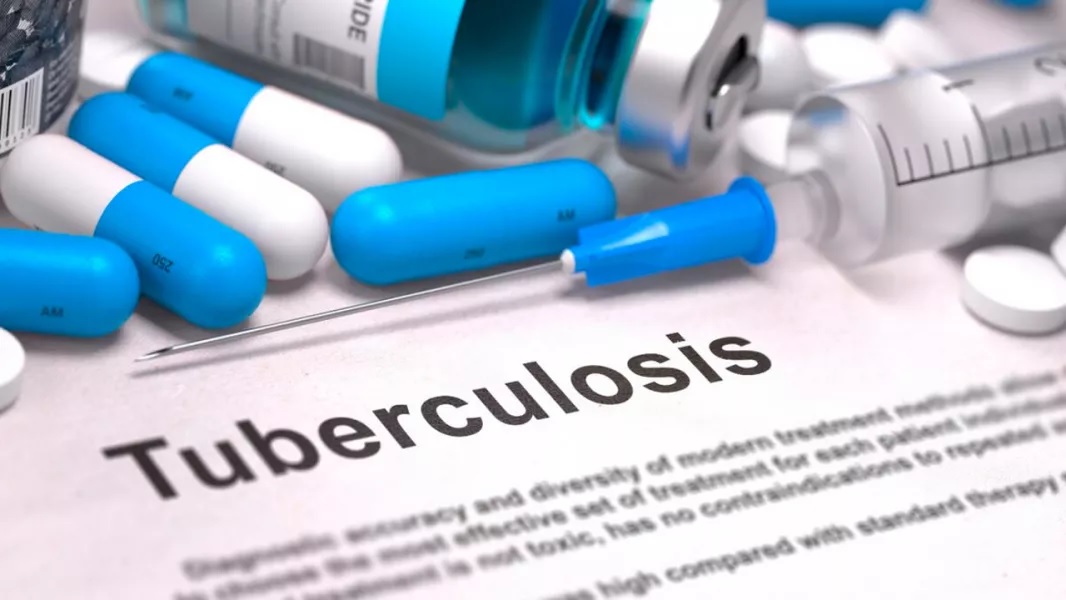

Salta: TUBERCULOSIS, POBREZA CON MILEI Y SÁENZ

Una enfermedad asociada a las condiciones inhumanas de la pobreza, azota al país ante el silencio de autoridades nacionales y provinciales.